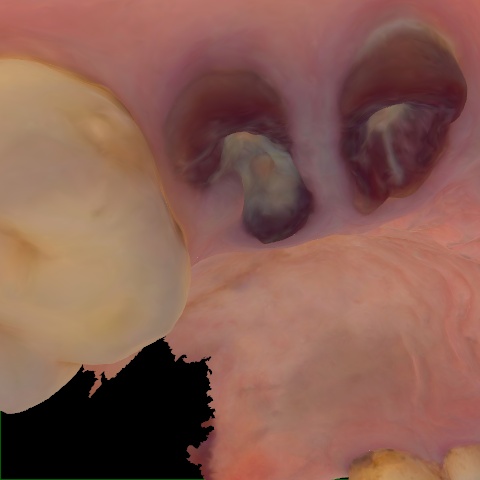

Image 1281 / 1743

NHD36692

Annotated as "Good"

Original Image Rendering Image